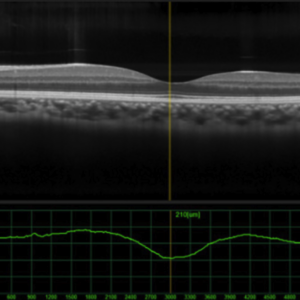

OCT has become a gold standard in the delivery of eye care to diagnose and manage posterior segment diseases of the optic nerve and retina, in particular, glaucoma and macular diseases. This six-part course provides a continual curriculum of OCT technologies, from basic physical science concepts to image interpretation, analysis, and management of pathology.